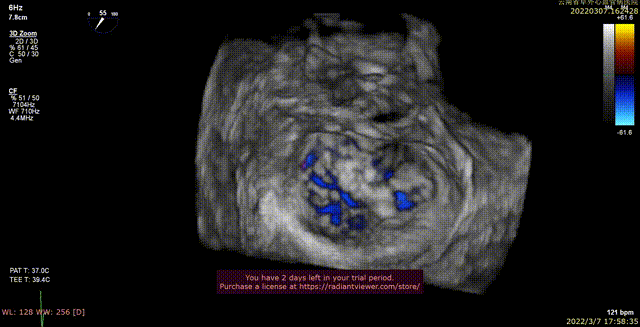

术前xPlane view提示:二尖瓣重度反流

术后xPlane view提示:二尖瓣反流显著减少

术前3D view提示:二尖瓣重度反流

术后3D view提示:二尖瓣反流显著减少